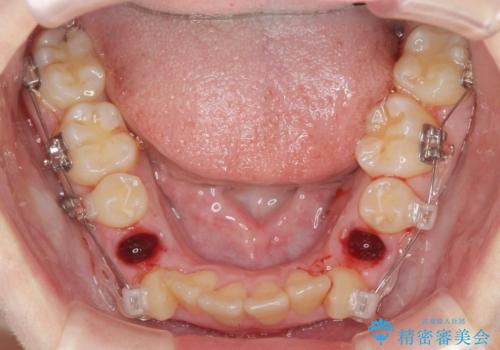

- 歯並びのがたつきにより歯ブラシがしづらく、今後虫歯になってしまう不安から、矯正治療を希望されて来院されました。

歯を並べるにはスペースが不足しているため、小臼歯の抜歯を4本行うマルチブラケット矯正による治療を計画します。